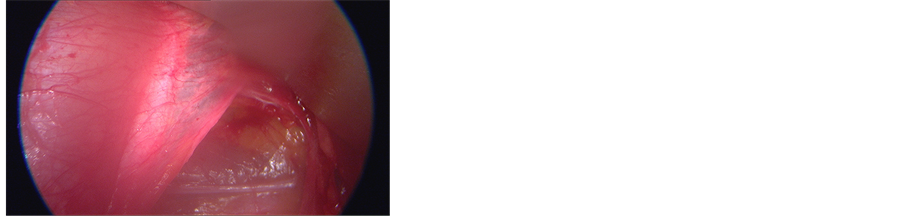

Figure 3. Intraoperative endoscopic view of the arcuate line (also known as linea semicircularis or Douglas’ line).

The retroperitoneal approach is our preferred technique because it respects the anatomy of the abdominal structures. The standard retroperitoneal approach is performed with a midline skin and under skin layer incision, with a left approach to the intra-abdominal structures. Different authors have proposed many variations to this technique. In 2012 a midline approach from the right side was proposed by Edgard-Rosa et al. [2] . In this paper the authors proposed a new mobilization technique of the vena cava to perform interbody fusions from L2 to L5, with an approach below the aortic bifurcation to L5-S1 disc. The authors reported four major venous injuries on a total of 469 patients included in the study. However, we prefer the left side approach because the first big vessel found during the approach is an artery (the common iliac artery). This decreases the risk of vascular injury because of the thicker walls of arteries in respect to veins. Authors preferred technique is performed with the patient lying in a supine position, with extended legs. A 3 - 5 cm transversal medial incision (for L5-S1 exposure) or a longitudinal left paramedian incision (for L4-L5 exposure) is performed (Figure 1). The anterior sheath of the rectus is cut and the muscle is retracted upward and laterally, to preserve nervous and bloody supply avoiding damages to the inferior epigastric vessels; the peritoneum and the left ureter are then gently pushed from the left to the right side (Figure 2) until the psoas muscle is seen. At this point the arcuate ligament is cut (Figure 3). This allows the widening of the working space and a better visualization of the deep structures. After the insertion of deep retractors, the big vessels are visualized and mobilized. For the L4-5 disc, aorta, cava and common iliac veins and arteries are retracted laterally from left to right after the ligature of the ileolumbar veins. The L5-S1 disc is located below aorta and cava bifurcation into the two common iliac arteries and veins, respectively. These vessels are then retracted on both sides to expose the disc, and the middle sacral vessels are coagulated with a bipolar forceps or ligated.